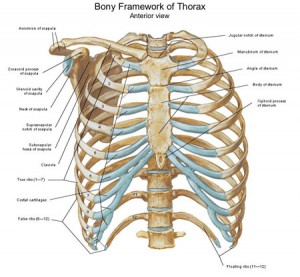

胸郭(写真1)は主に12個の胸椎と12対の肋骨、1個の胸骨から構成されていて、人間にとって大切な心臓や肺など無くてはならない臓器を収めまっています。

鳥かご状の形をした胸郭には胸鎖乳突筋、胸骨舌骨筋、胸骨甲状筋、鎖骨下筋、大胸筋、小胸筋、広背筋、斜角筋、前鋸筋、外肋間筋、内肋間筋、腹直筋、外腹斜筋、内腹斜筋、、腹横筋、横隔膜、胸腸肋筋、腰腸肋筋、胸最長筋、上後鋸筋、下後鋸筋など多数の筋肉が関与しています。